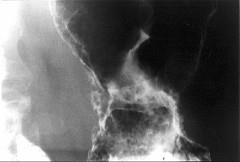

问题 男,65岁,中上腹痛半年,X线检查如图,最可能的诊断是()

选项 A.胃息肉 B.胃溃疡 C.胃浸润癌 D.胃间质瘤 E.糜烂性胃炎

答案 C